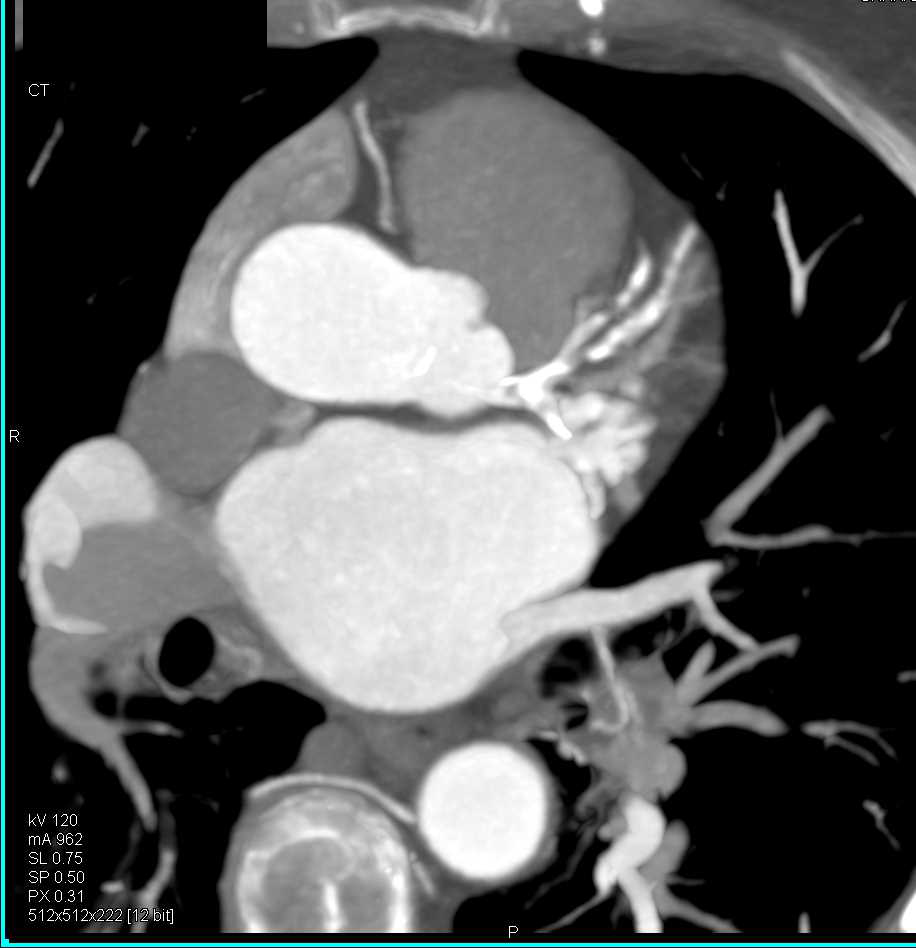

Type A Dissection Extending into the Right Subclavian Artery